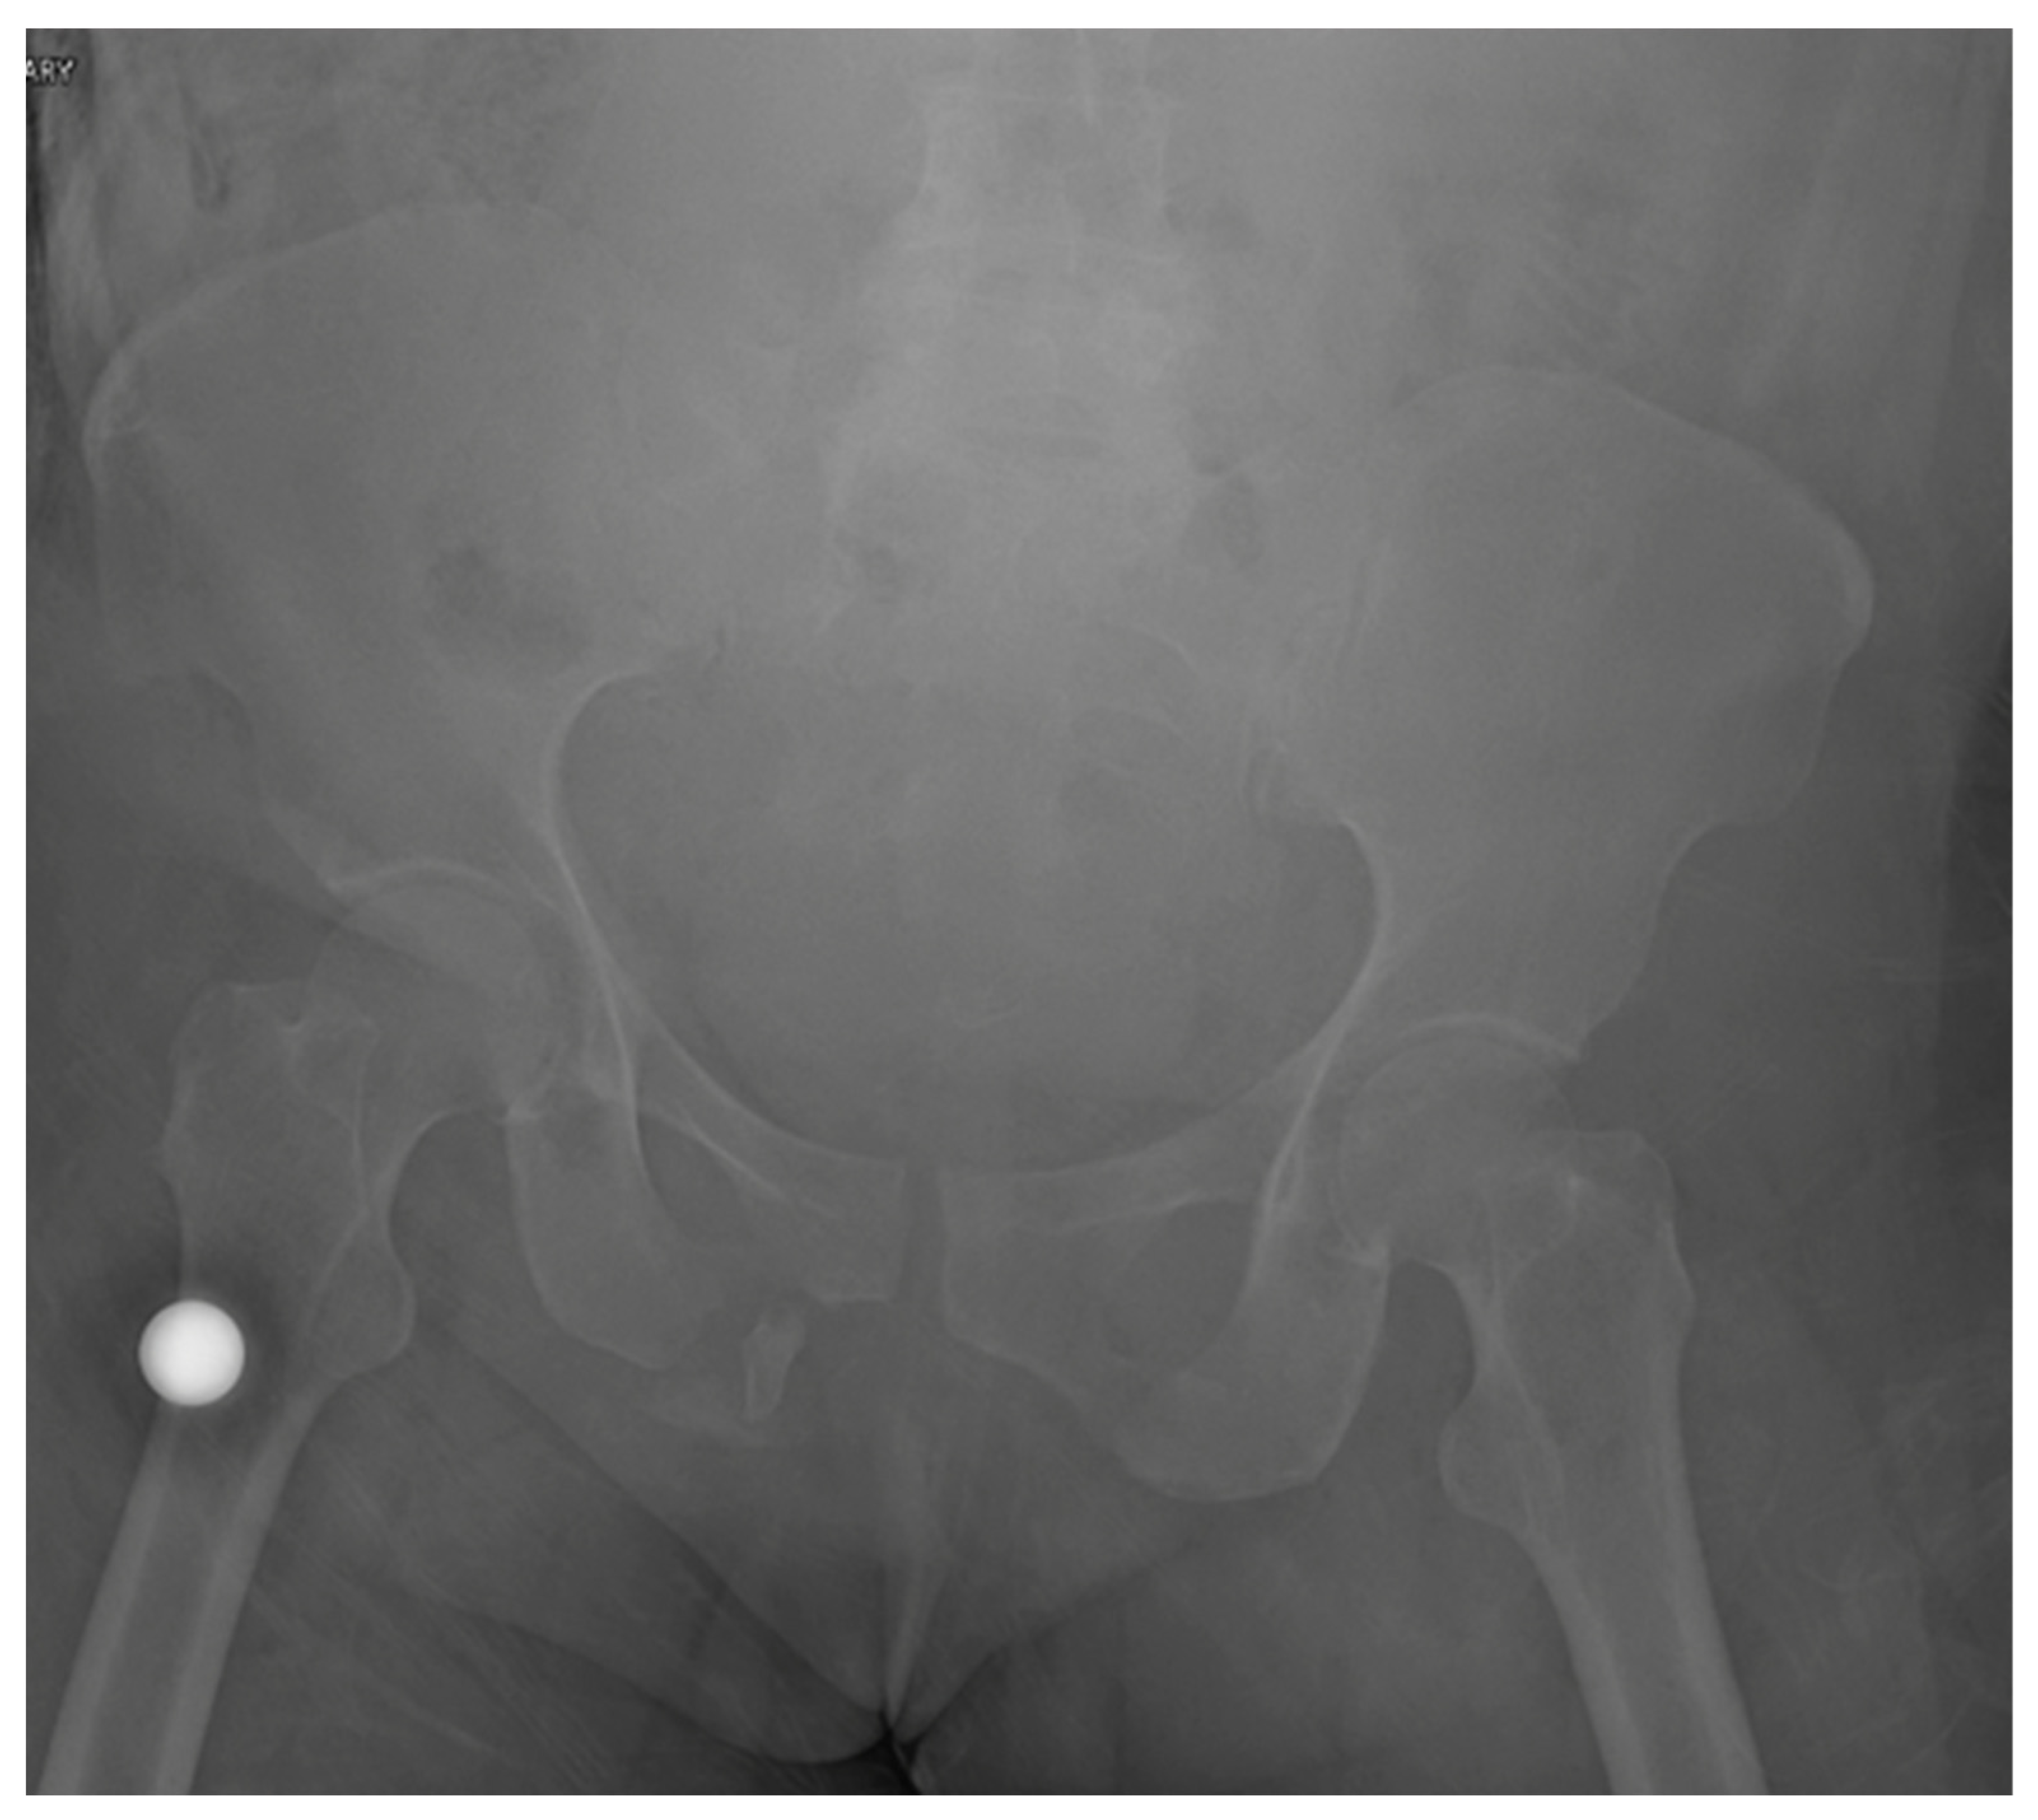

A 59-year-old female with no known past medical history presented to our level 1 trauma center, having been involved in a rollover motor vehicle collision. Plain radiographs and CT imaging demonstrated various orthopedic injuries including a Dennis type 1 vertical shear sacral fracture, bilateral superior and inferior pubic rami fractures (Figure 1 and Figure 2), right T5–T6, L1–L5, and left L2–L3 transverse process fractures, spinous process fractures of T7 and T9, and right posterior rib 4–7 fractures. Additional, non-orthopedic injuries included pneumothorax, retroperitoneal hematoma, grade 4 hepatic injury, grade 3 splenic injury, and grade 2 kidney injury. On day 3 of presentation, the patient was stable enough for operative fixation from the orthopedic surgery team.

Figure 1.

The original injury film on an AP pelvis in a skeletally mature individual demonstrating a vertical shear sacral fracture, bilateral superior and inferior pubic rami fractures.